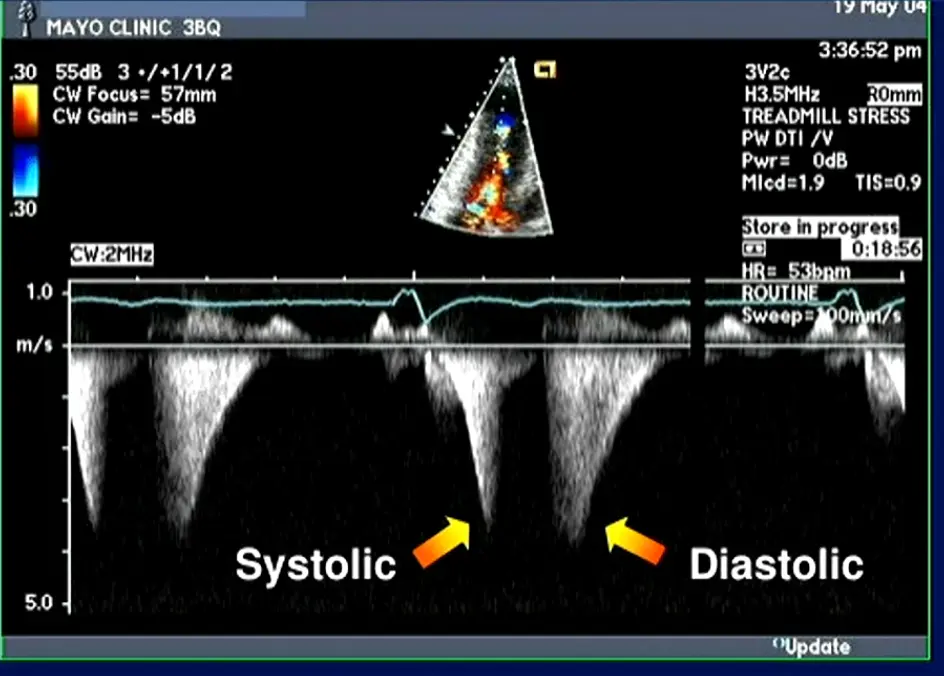

LVOT obstruction is assessed using Continuous Wave Doppler-derived peak instantaneous gradient

⚠️ Make sure you are not getting the MR jet. Easy to happen b/c the MR jet is right next door to the LVOTO.

- MR jet is more rounded

Classically described as having a “dagger”-shaped appearance, but honestly resembles more of a nonworking upper edge of a Bowie knife. 2 Dr. Saghir also used the term “dragon’s tooth,” which I like.

Gradients > 60 mmHg may take on a “lobster claw” pattern 2